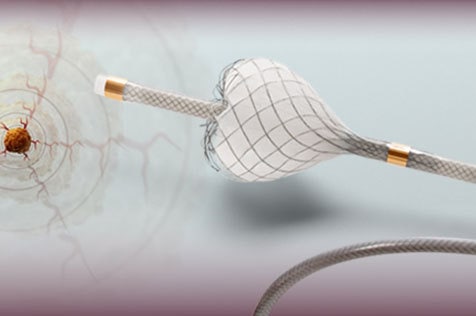

Think we’re joking? We’re not. At SFC Group, we stand out for all the right reasons. A couple on the beach? That’s just wrong. Scroll down for what’s right.